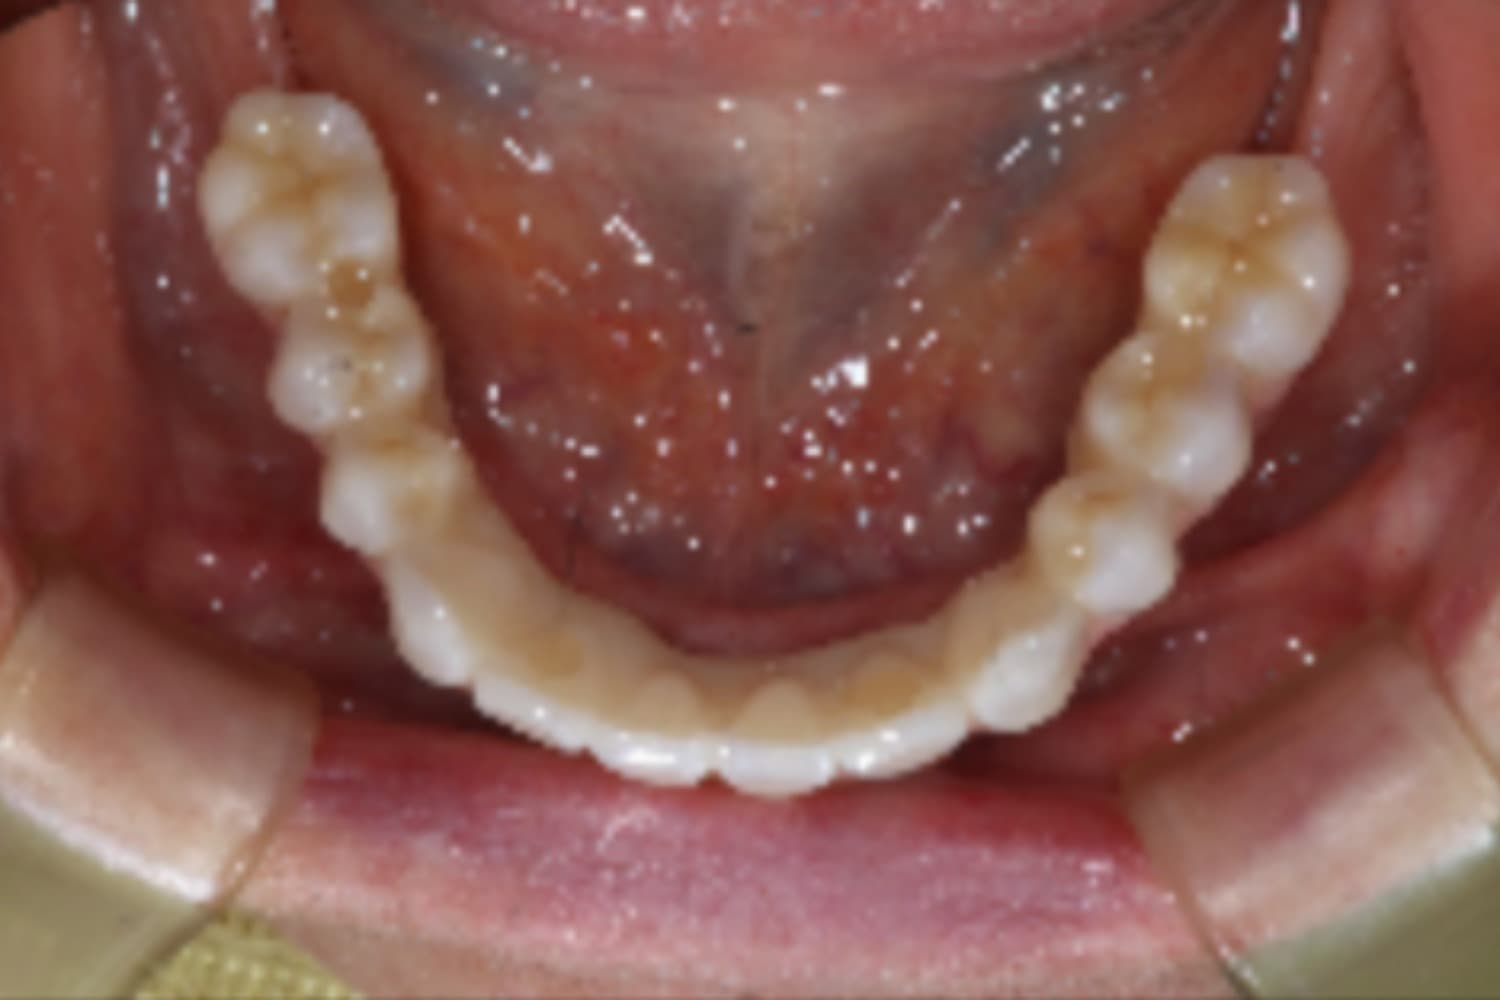

下顎すべてのインプラント治療

Before

After

下の前歯は抜歯と同時にインプラント4本を埋入し、その日に仮歯を装着してます(All-on-4)。

主訴

下の前歯がぐらぐらする

治療期間

6カ月

治療回数

12回

費用

3,080,000円

副作用・リスク

・インプラント埋入時の神経損傷リスクがあります。